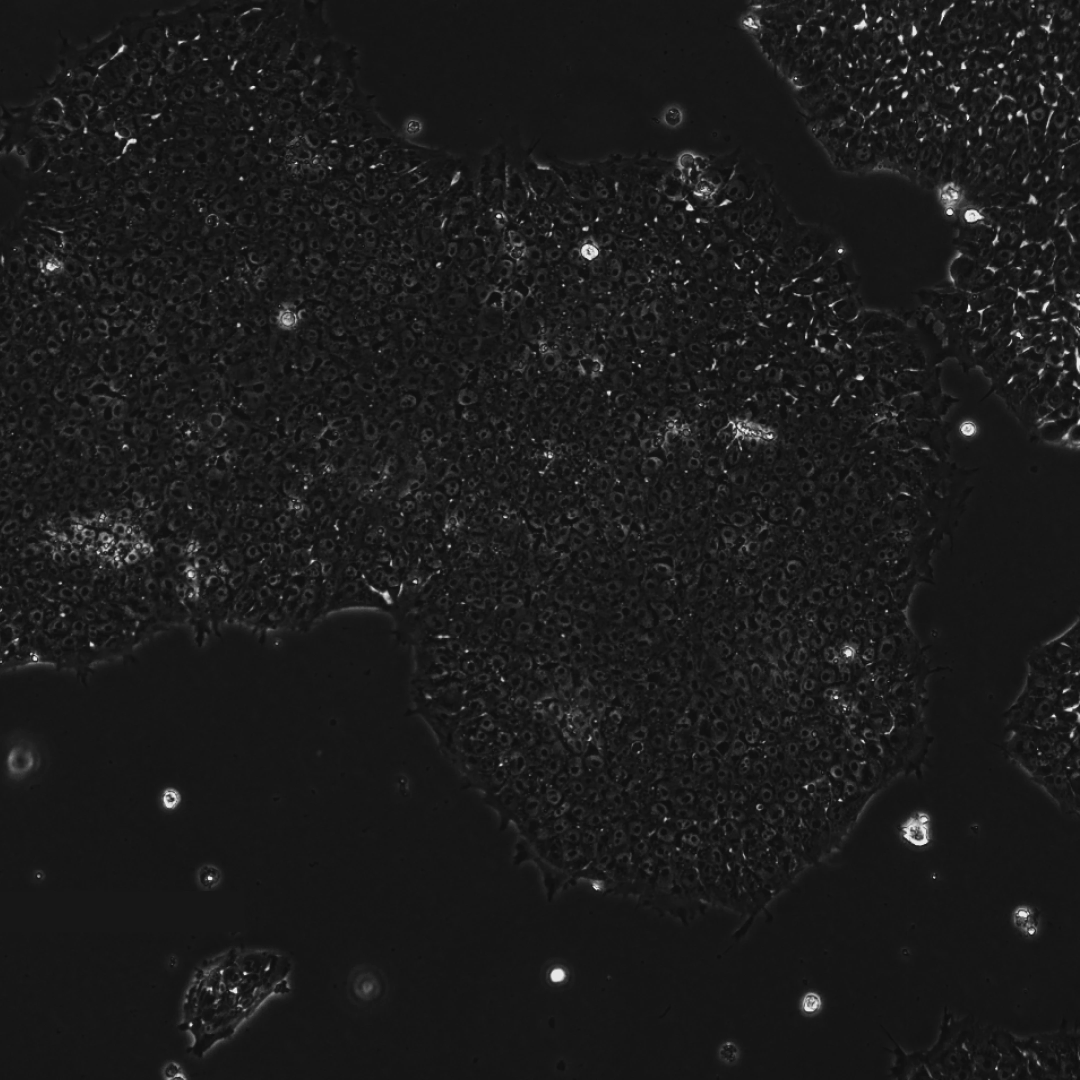

下面这三张图展示的是,OpenAI 设计的蛋白质能更高效地诱导干细胞重编程:

下图显示,在初步筛选(Pilot)、RetroSOX 筛选和 RetroKLF 筛选中,表达早期多能性标记物 SSEA4(左柱)和晚期标记物 TRA-1-60(右柱)的细胞百分比。

可以看到,与效率极低(<0.1%)的常规方法相比,RetroKLF 显著提升了两种标记物的表达水平。

下面两张图展示的是,AI 设计方法的阳性率和序列编辑深度。

可以看到,将顶尖的 RetroSOX 和 RetroKLF 变体组合使用,带来了最大的性能提升。

在三次独立的实验中,成纤维细胞的早期(SSEA-4)和晚期(TRA-1-60, NANOG)标记物水平均出现急剧上升,且晚期标记物的出现时间比使用野生型 OSKM 组合方案提前了数天。

此外,研究团队在第 10 天通过碱性磷酸酶(AP)染色对 RetroSOX 和 RetroKLF 变体进行了验证。

结果显示,形成的细胞集落不仅表达晚期多能性标记物,还表现出强大的 AP 活性,这是细胞具备多能性的有力标志。

下面三张图中所有的结果共同证实了,研究团队已成功获得健康、且完全重编程的干细胞,从而也全面验证了重编程干细胞的健康与功能。